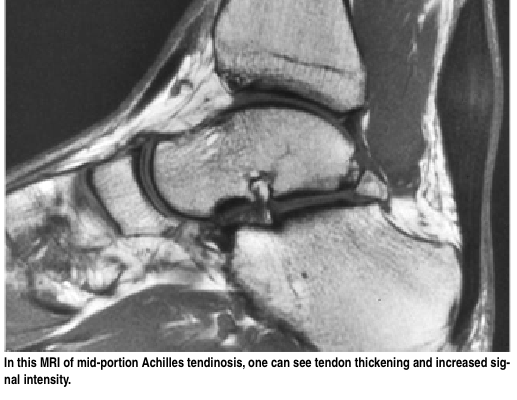

•  만성 건병증 (Chronic tendinopathy) : 만성 건병증은 MRI상으로 거대화된 비정상적인 모양의 힘줄로 보인다.

△ Achilles tendonosis MRI

(http://www.podiatrytoday.com/conservative-care-mid-portion-achilles-tendinopathy)